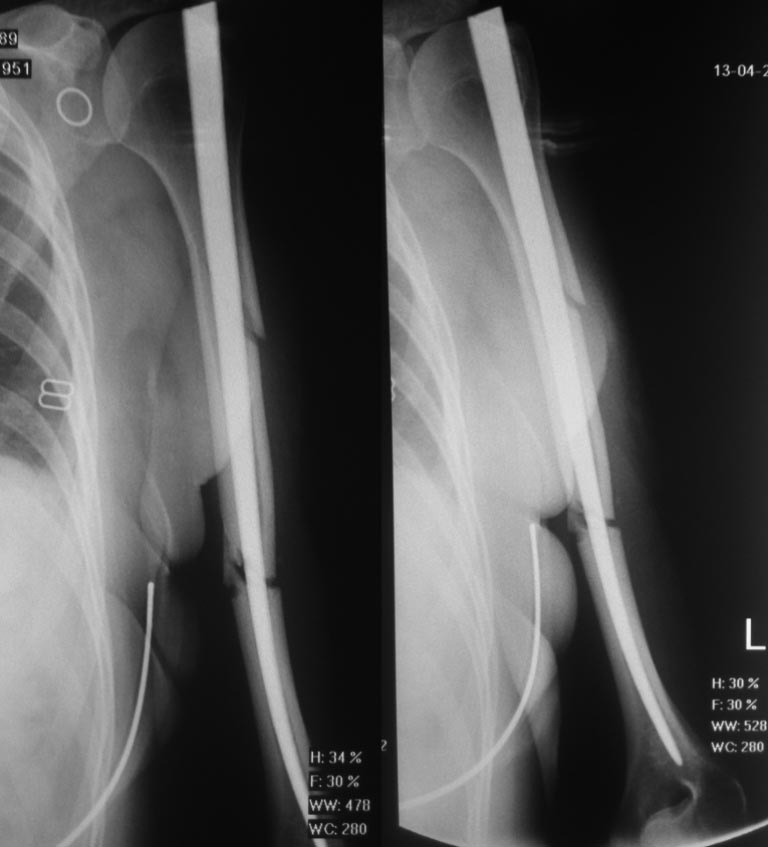

Спасибо вам большое за ответ! Вот снимки с первой операции - от

13.04.2016, с повторного приема через две недели после операции.